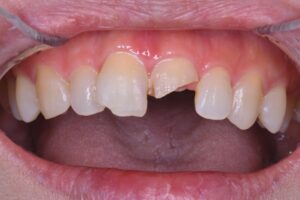

医院ブログ 2026/03/08

【表参道 歯科 ダイレクトボンディング】 破折した... こんにちは。表参道・青山にある歯科石上医院です。 自転車の交通事故…